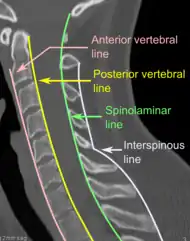

On CT scan or X-ray, a cervical fracture may be directly visualized. In addition, indirect signs of injury by the vertebral column are incongruities of the vertebral lines,[7] and/or increased thickness of the prevertebral space:[8]

X-ray of normal congruous vertebral lines

X-ray of normal congruous vertebral lines